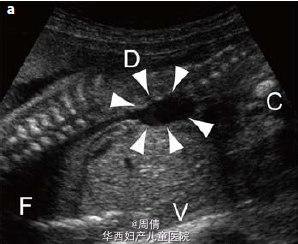

1,2.超声提示在大动脉分叉点以上的降主动脉上有一个动脉瘤,最大直径2cm 3,可见扩大的左脑室和变薄的左侧大脑实质 4,30周时胎儿MRI提示颅腔内的左侧脑室有一个增大的囊性结构